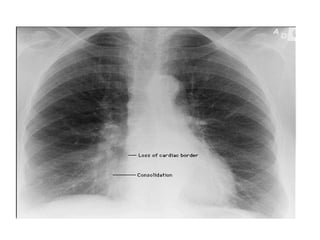

Loss of Sharp Costophrenic Angles

Loss of SharpCostophrenic Angles